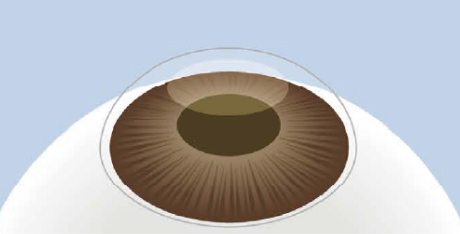

SMILE(Small Incision Lenticule Extraction)は、ドイツのCarl Zeiss 社が開発した次世代近視矯正レーザー手術です。SMILEはアメリカ・ヨーロッパ・アジアを中心に80か国以上で11,000,000件以上の実績があります。この手術は、角膜に2~3mm程度の小さな切開を加え、内部のレンチクル(円盤状の角膜組織)を取り除くことで視力を矯正します。これにより、自然な角膜構造を保ちながら、痛みや合併症のリスクを最小限に抑えることが可能になりました。従来のLASIK手術に比べて角膜への侵襲が少なく、ドライアイのリスクも軽減するとされています。

レンチクルの形成

フェムトセカンドレーザーを使用し、

角膜の内部に微細なレンチクルを

形成します。

小切開の作成

約2~4mmの小さな切開を

角膜表面に作成します。

レンチクルの摘出

作成した切開部からレンチクルを丁寧に取り出します。これにより角膜の屈折力が変化し、視力が矯正されます。

自然治癒を待つ

縫合も不要で、

切開部は自然に癒合します。